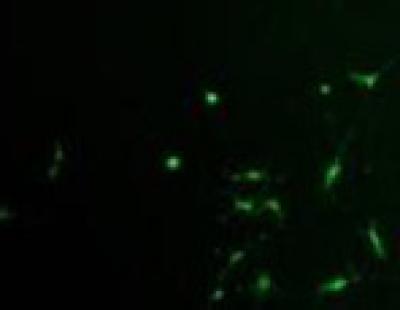

A series of previous studies suggested that the neuronal differentiation rate of bone marrow mesenchymal stem cells during the in vitro culture reached 78-92%, but their in vivo transplantation efficiency, and survival and differentiation rates were very low. The low levels of bone marrow mesenchymal stem cell transplantation, survival, colonization and differentiation efficacy greatly restrict their therapeutic effect. Red or near-infrared light from 600-1,000 nm promotes cellular migration and prevents apoptosis. Thus, Dr. Xiaoying Wu and co-workers from Chongqing University in China hypothesized that the combination of red light with bone marrow mesenchymal stem cell transplantation would be effective for the treatment of hypoxic-ischemic brain damage. They found that, after a 40-hour irradiation under red light-emitting diodes at 660 nm and 60 mW/cm2, an increasing number of green fuorescence-labeled bone marrow mesenchymal stem cells migrated towards hypoxic-ischemic damaged primary neurons. Meanwhile, neonatal rats with hypoxic-ischemic brain damage were given an intraperitoneal injection of 1 × 106 bone marrow mesenchymal stem cells, followed by irradiation under red light-emitting diodes at 660 nm and 60 mW/cm2 for 7 successive days. Shuttle box test results showed that, after phototherapy and bone marrow mesenchymal stem cell transplantation, the active avoidance response rate of hypoxic-ischemic brain damage rats was significantly increased, which was higher than that after bone marrow mesenchymal stem cell transplantation alone. Experimental findings, published in the Neural Regeneration Research (Vol. 9, No. 3, 2014), indicate that 660 nm red light emitting diode irradiation promotes the migration of bone marrow mesenchymal stem cells, thereby enhancing the contribution of cell transplantation in the treatment of hypoxic-ischemic brain damage